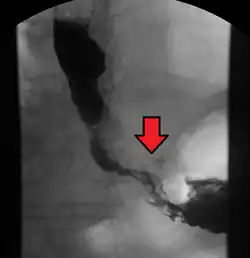

Although an occlusive tumor may be suspected on a barium swallow or barium meal, the diagnosis is best made with an examination using an endoscope. This involves the passing of a flexible tube with a light and camera down the esophagus and examining the wall, and is called an esophagogastroduodenoscopy. Biopsies taken of suspicious lesions are then examined histologically for signs of malignancy.

Additional testing is needed to assess how much the cancer has spread (see § Staging, below). Computed tomography (CT) of the chest, abdomen and pelvis can evaluate whether the cancer has spread to adjacent tissues or distant organs (especially liver and lymph nodes). The sensitivity of a CT scan is limited by its ability to detect masses (e.g. enlarged lymph nodes or involved organs) generally larger than 1 cm.[44][45] Positron emission tomography is also used to estimate the extent of the disease and is regarded as more precise than CT alone.[46] PET/MR as a novel modality has shown promising results in preoperative staging with fair feasibility and good correlation in comparison to PET/CT. It can enhance tissue differentiation with lowering the radiation dose to the patient.[47] Esophageal endoscopic ultrasound can provide staging information regarding the level of tumor invasion, and possible spread to regional lymph nodes.